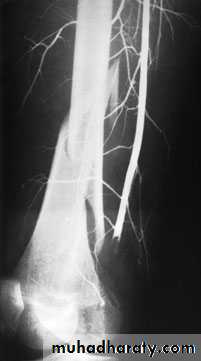

Infection.Vascular injury.